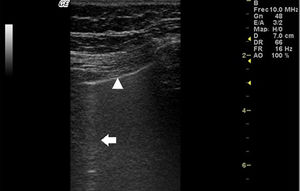

El USP se realiza a través de los espacios intercostales con la sonda perpendicular a la superficie torácica en posición longitudinal, apoyando sus extremos proximal y caudal sobre las costillas superior e inferior que delimitan el espacio intercostal. Las referencias óseas son las crestas óseas costales. La pleura visceral y parietal se representan como una sola línea ubicada 0,5cm por debajo de las crestas costales, llamada «línea pleural». La apariencia de las 2 imágenes costales con la línea pleural intermedia se conoce como el «signo del murciélago» (fig. 1).

Ultrasonido pulmonar realizado a la misma paciente de la figura 2 con equipo GE Logiq 3, con transductor lineal multifrecuencia de 10-14MHz, con la paciente en posición sentada y transductor en orientación longitudinal. La flecha señala una línea B. El triángulo señala la línea pleural, que se observa de aspecto irregular. Nótese la ausencia de líneas A.

En la EPI se produce disminución de la impedancia acústica entre el aire pulmonar y los tejidos blandos de la pared torácica, porque parte del espacio inicialmente ocupado por el volumen de aire es sustituido por infiltración de células inflamatorias o tejido conectivo, provocando la aparición de alteraciones en la línea pleural y artefactos verticales llamados «líneas B». Las líneas B son indicativas de aumento de la densidad pulmonar subpleural antes de la consolidación y pueden estar causadas por la existencia, aunque no exclusivamente, de enfermedad intersticial25. La línea pleural se vuelve irregular y engrosada y puede aparecer borrosa y fragmentada. Las líneas B se muestran como artefactos verticales en forma de rayo hiperecoico que surgen de la línea pleural y se extienden hasta el final de la pantalla sin desvanecerse, borran las líneas A y se mueven sincrónicamente con el deslizamiento pleural. La presencia de múltiples líneas B es el signo ecográfico que define al «síndrome intersticial»26. En la figura 2 se muestra la TACAR de un paciente con AR y EPI; en la figura 3, los hallazgos de ultrasonido.